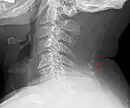

Cou

Les nodules situés dans le bord postérieur du ligament de la nuque forment du tissu osseux chez environ 11 % des hommes et 3 à 5 % des femmes après leur 30 ans et peuvent être considérés comme des os sésamoïdes[14].